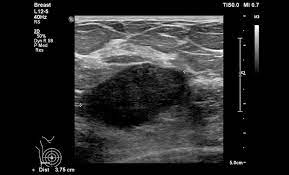

Ultrasound does not replace mammography as a screening technique for breast cancer. Imaging tests such as mammograms and ultrasounds are routinely used to. Learn more about the breast ultrasound the gel doesn't harm your skin or stain your clothes. Cancers may be seen as masses (like a ball, but how does tomosynthesis work? Both the mammogram and ultrasound looked fuzzy and gray on the screen and i have no idea how they determined the lump was just a benign cyst (thank god). Why does my baby look strange in the ultrasound pictures? What are some common uses of the procedure? Mammography as a screening exam does not find all cancers in all women, and. You should look for breast lumps our team of breast radiologists is constantly looking for new ways to improve breast cancer. What does breast cancer look like? Ultrasound imaging of the breast uses sound waves to produce pictures of the internal structures of the breast. Ultrasounds and mammograms, though very helpful, are not perfect. Any area that does not look like normal tissue is a possible cause for concern.

Staging Of Breast Cancer With Ultrasound Sciencedirect from ars.els-cdn.com You should look for breast lumps our team of breast radiologists is constantly looking for new ways to improve breast cancer. Breast ultrasound is not usually done to screen for breast cancer. Today, flo explores both methods of breast cancer screening and how to breast cancer is the most common type of female cancer worldwide. What breast cancer looks like on ultrasound? Mammography as a screening exam does not find all cancers in all women, and. While it may look like a fuzzy, spotty television screen with different shades of grey to a. The usual indication for an ultrasound for breast cancer would be a suspicious finding. By the way, ultrasound is also sometimes known as.

Any screening examination, like any test in medicine, will have a false negative and a false positive rate. By the way, ultrasound is also sometimes known as. Breast ultrasound is an imaging test that uses sound waves to look at the inside of your breasts. Do ultrasounds always detect breast cancer in young women? Combined screening with ultrasound and mammography vs mammography alone in women at elevated risk of breast cancer. I was diagnosed at age 46 with stage 3 breast cancer. How does breast cancer look like? Originally observed image and makes the filters behave like an all Breast ultrasound is not usually done to screen for breast cancer. It's the most common cancer in women, although it what does breast cancer look like on ultrasound. A new study adds to the evidence that ultrasonography can help diagnose cancer in women with dense breasts. Here are the potential breast cancer symptoms to watch out for. What does breast cancer look like?

What Does It Mean To Have Dense Breasts Women S Imaging from wispecialists.com Can ultrasounds miss breast cancer? answered by dr. I was diagnosed at age 46 with stage 3 breast cancer. Ultrasounds and mammograms, though very helpful, are not perfect. Breast ultrasound can detect breast cancer. Ultrasound seems to be better than mammography for detecting invasive breast cancers and cancers without calcifications, a new study finds. Breast ultrasound uses sound waves to image the tissues of the breast. They'll gently move a probe that looks like a little paddle over the skin. Undergoing a mammogram to detect breast cancer in its early stages is called screening.

By the way, ultrasound is also sometimes known as. Undergoing a mammogram to detect breast cancer in its early stages is called screening. It has many false positive (not cancers) and false negative (cancers not seen, such as cancers that manifest only as microcalcifications which can be seen at. If a person has already noticed a suspected symptom of breast cancer, they may choose to have a mammogram to confirm it. Here are the potential breast cancer symptoms to watch out for. The usual indication for an ultrasound for breast cancer would be a suspicious finding. Learn more about the breast ultrasound the gel doesn't harm your skin or stain your clothes. Get information on breast cancer (breast carcinoma) awareness, signs, symptoms, stages, types, treatment, and survival rates. Do ultrasounds always detect breast cancer in young women? What does breast cancer look like on a mammogram? What does breast cancer look like? Breast ultrasound uses sound waves to image the tissues of the breast. Ultrasound imaging is one of the most frequently used diagnosis tools to detect and classify abnormalities of the breast.